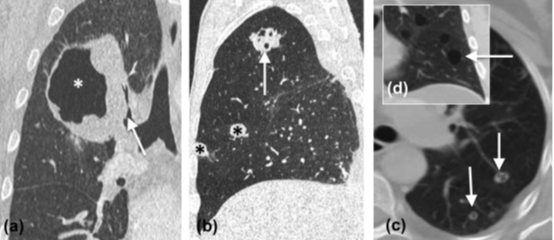

3. 形成空洞最常见的支气管来源恶性肿瘤是鳞状细胞癌(图1),其次是腺癌和大细胞癌。形成空洞最常见的转移性肿瘤同样是起源于头颈部或盆部、食管的鳞状细胞癌,其次是腺癌(图1)。

4. 在淋巴瘤样肉芽肿和淋巴瘤(多发病变、上叶为主)或HIV感染者的卡波西肉瘤中也可见空洞形成。厚壁、洞壁不规则和壁结节强化提示恶性空洞的可能性大。

图1 (a)不规则厚壁空洞(*),右肺上叶后段支气管闭塞(箭头)。病理:差分化鳞状细胞癌。(b)子宫内膜癌切除术后,右肺尖空洞(箭头),双肺多发大小不等结节(*)。(c)双肺弥漫性含空洞结节(箭头),符合转移。(d)经甲地孕酮治疗后,病灶洞壁变薄(箭头)。